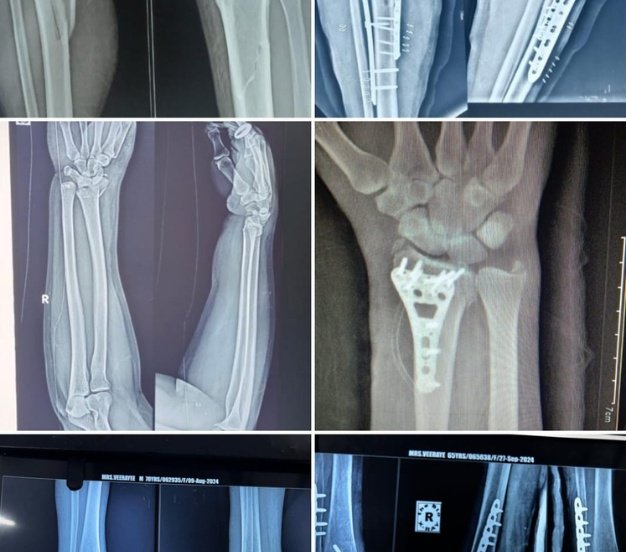

Operative X-rays